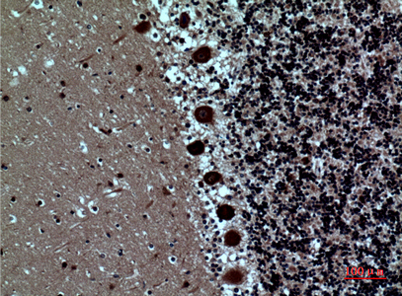

Product name: SAMHD1 rabbit pAb

Dilutions: Western Blot: 1/500 - 1/2000. IHC-p: 1/100-1/300. ELISA: 1/20000. Not yet tested in other applications.

Immunogen: The antiserum was produced against synthesized peptide derived from the Internal region of human SAMHD1. AA range:431-480

Background: SAM and HD domain containing deoxynucleoside triphosphate triphosphohydrolase 1(SAMHD1) Homo sapiens This gene may play a role in regulation of the innate immune response. The encoded protein is upregulated in response to viral infection and may be involved in mediation of tumor necrosis factor-alpha proinflammatory responses. Mutations in this gene have been associated with Aicardi-Goutieres syndrome. [provided by RefSeq, Mar 2010],